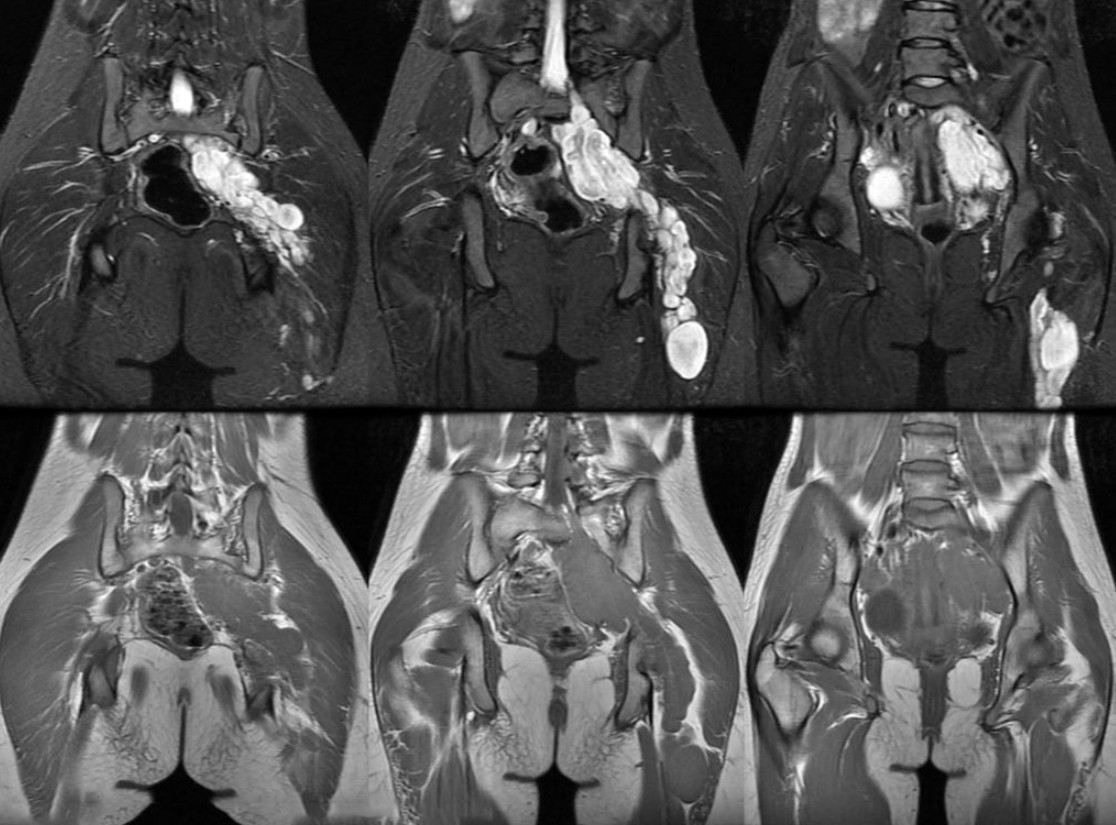

МРТ малого тазу є надзвичайно корисним інструментом для виявлення різних патологій та захворювань жіночого репродуктивного організму. Серед основних показників для проведення МРТ у гінекології включаються:

1. Міома матки: МРТ дозволяє точно визначити розмір, розташування та обсяг міоми, що допомагає в лікувальному плануванні.

2. Ендометріоз: Цей метод дослідження дозволяє визначити розподіл ендометріозних очагів та їхній вплив на прилеглі структури.

3. Запальні процеси: МРТ може виявити запальні процеси у прилеглих тканинах та органах.

4. Розриви та пухлини яєчників: МРТ надає можливість оцінити стан яєчників та виявити будь-які утворення.

Визначення обсягу патологій

Однією з головних переваг МРТ у гінекології є можливість точно визначити обсяг патологічних процесів. Це допомагає лікарям визначити оптимальний метод лікування та спрогнозувати результати. Наприклад, при наявності міоми матки МРТ може показати, чи є необхідність у хірургічному втручанні, або чи можливо провести консервативне лікування.